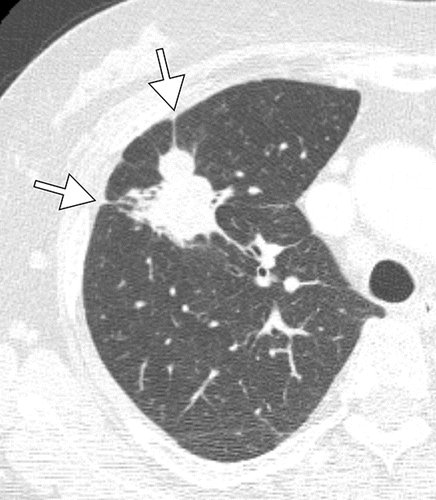

What are the CT characteristics of T790M mutation--positive non--small cell lung cancer after tyrosine kinase inhibitor therapy failure? Find out in this article by Koo et al.pic.twitter.com/CEw1GK4Ku0